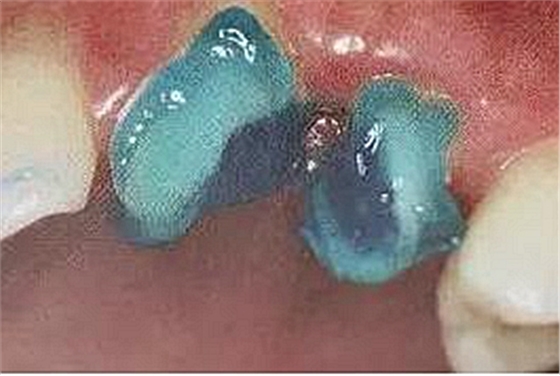

透光性

纖維樁的透光性很重要,因為粘接時使用的是光固化樹脂,光源必須能夠透過纖維樁照到周圍的粘接劑。

請看幾個不同透光性能對比。